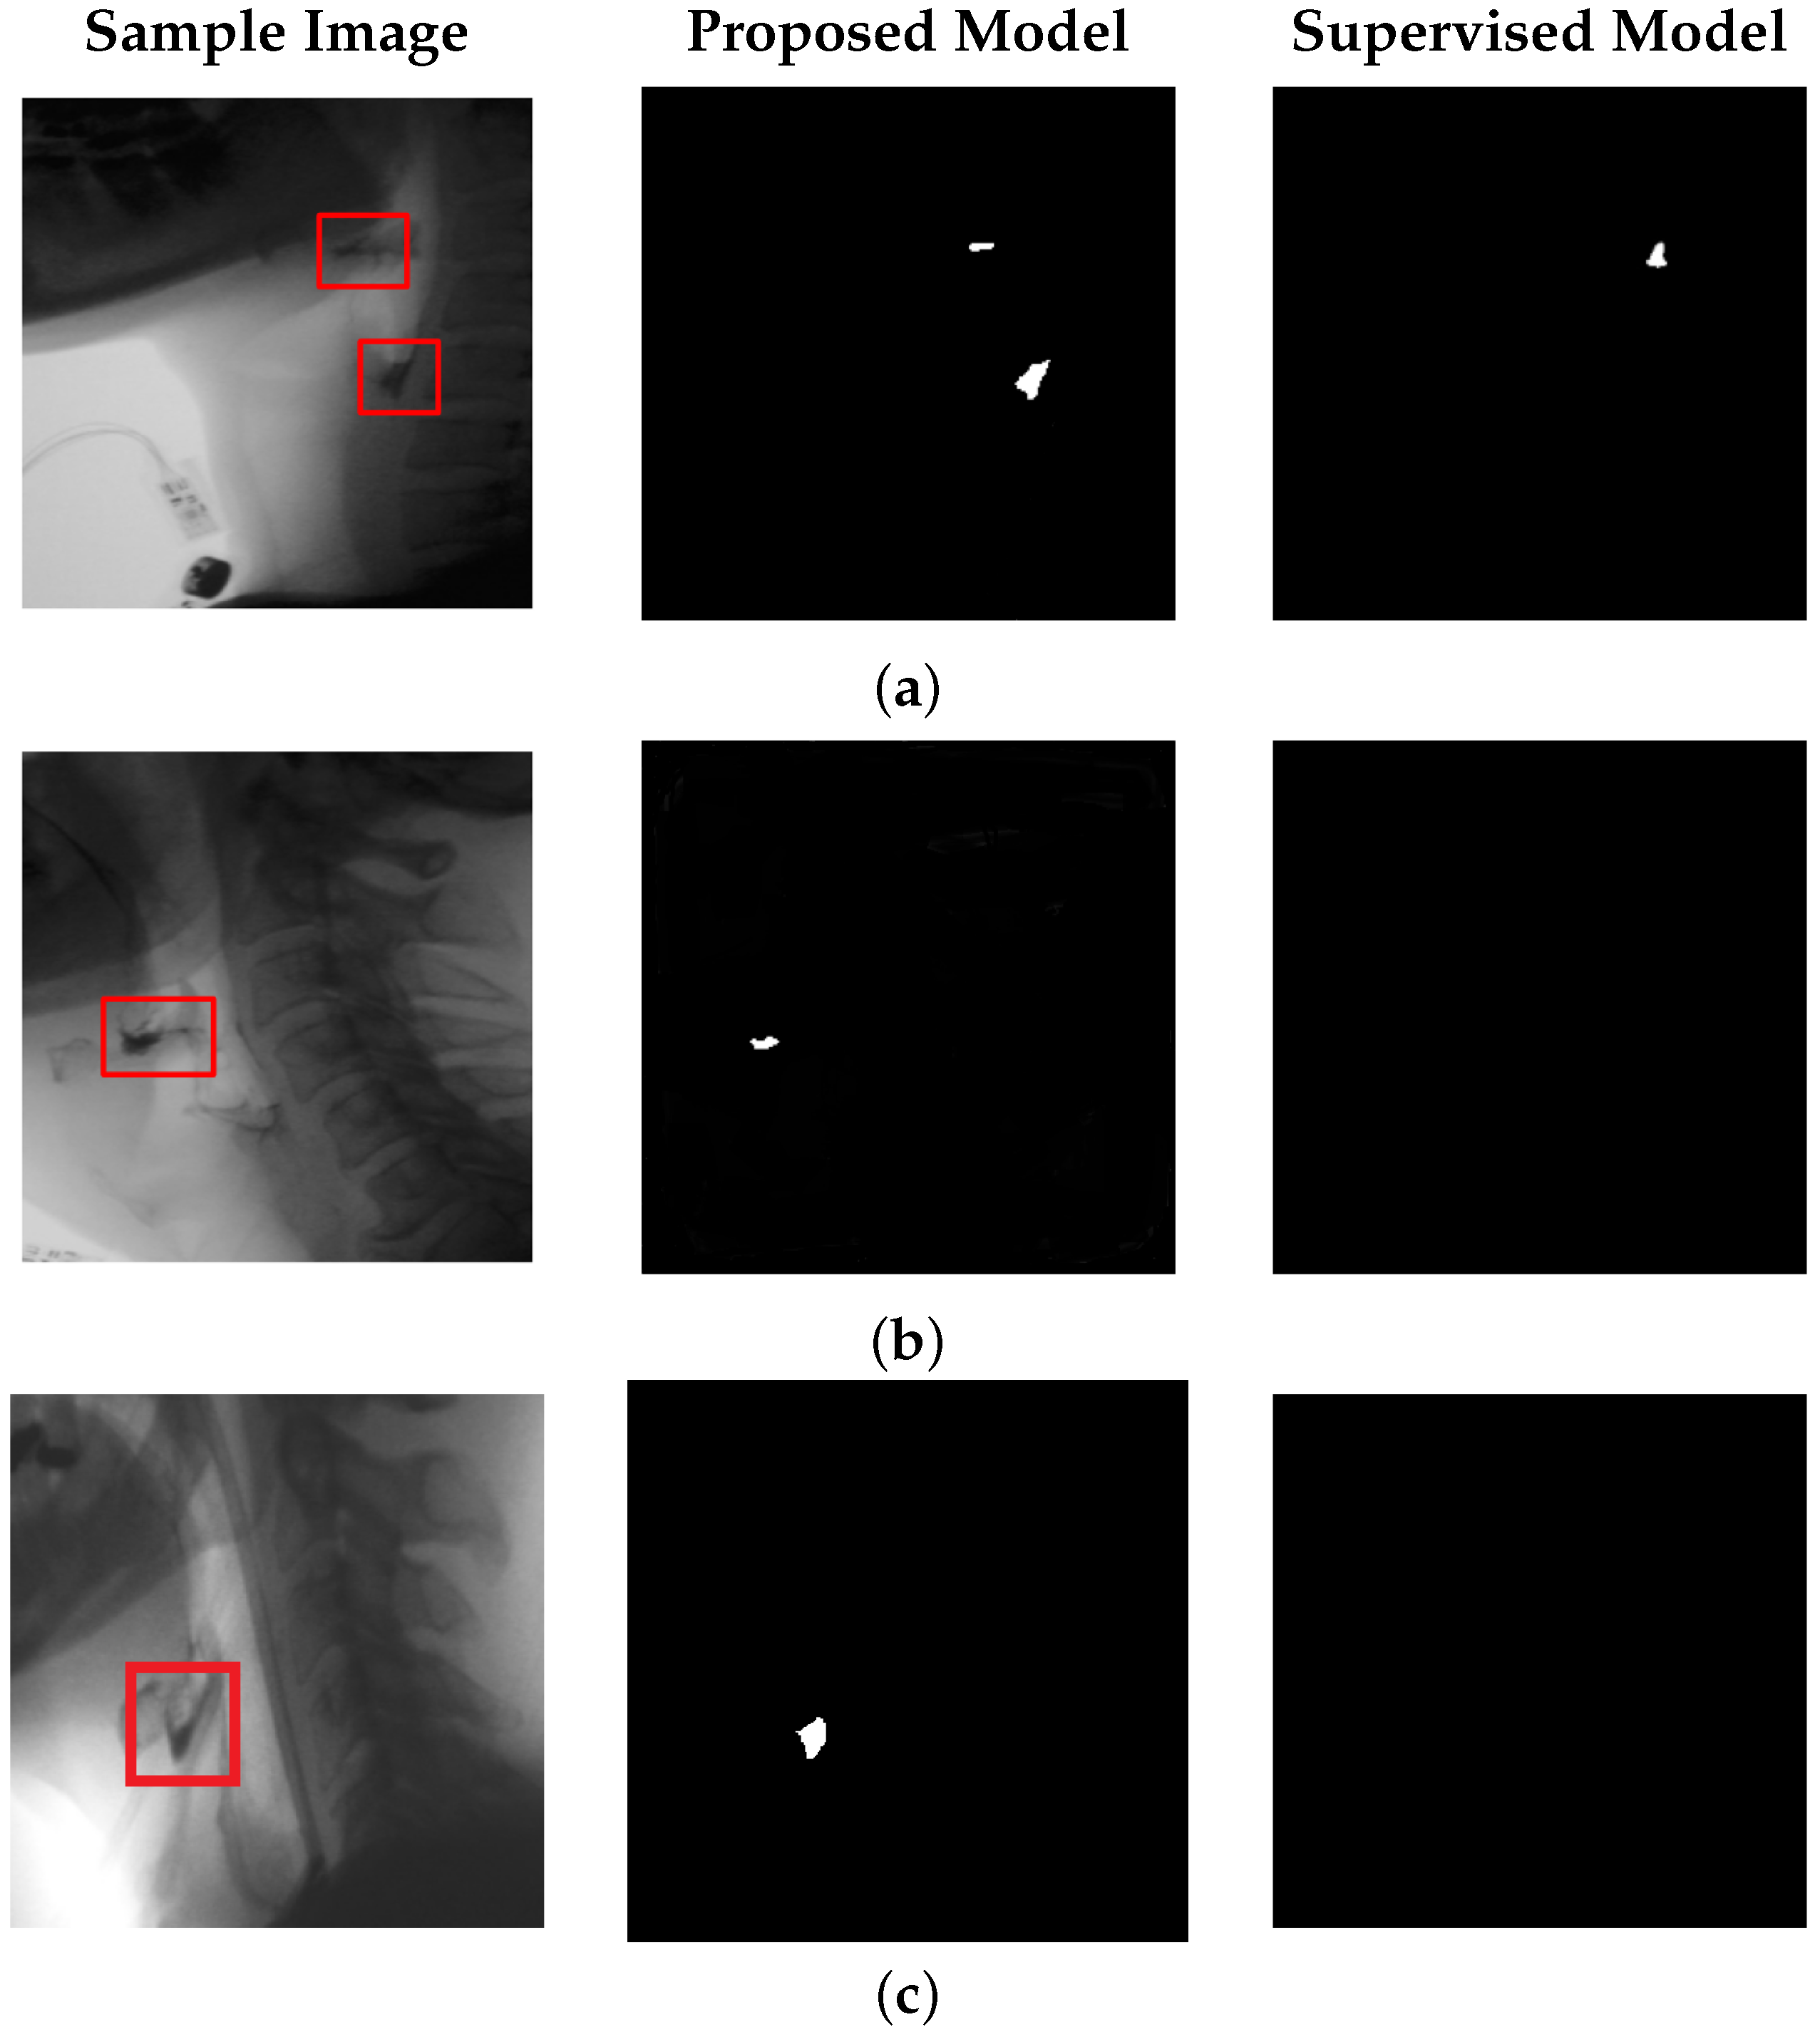

Figure 4 illustrates representative test frames containing bolus, along with their corresponding ground truth annotations, predictions from the proposed model, and segmentation results from the supervised model presented in [14], which reports state-of-the-art performance for automatic bolus segmentation. Notably, the supervised model was originally trained on a dataset acquired using the same VFSS imaging device and curated by the same clinical team, making this comparison particularly relevant and reliable. This consistency ensures that observed differences in performance are attributable to methodological differences rather than domain shift or annotation bias.

Figure 4c illustrates a case of bolus discontinuity, where two distinct bolus regions appear within the same frame. This spatial separation increases the complexity of the detection task compared to single-region bolus cases. Despite this challenge, the model demonstrates reasonable accuracy in identifying both regions. Overall, the model performs well in bolus detection; however, its accuracy declines in frames where the bolus remains within the oral cavity, as shown in Figure 4d. This limitation is primarily due to the lower spatial resolution of the imaging equipment in the oral region, which reduces the visibility of fine structural details and contrast variations necessary for accurate segmentation. Notably, the supervised baseline model also exhibits reduced performance in this scenario, highlighting the inherent difficulty of detecting the bolus in the oral phase. As a result, both models struggle to reconstruct and segment the bolus accurately in this region.

Figure 4. Qualitative results of bolus segmentation using the proposed model with positional encoding. Each group of four columns corresponds to a test case. From left to right within each group: (a) original VFSS frame, (b) ground truth segmentation mask, (c) prediction by the proposed unsupervised model, and (d) prediction by the supervised model from [14], representing a state-of-the-art benchmark.